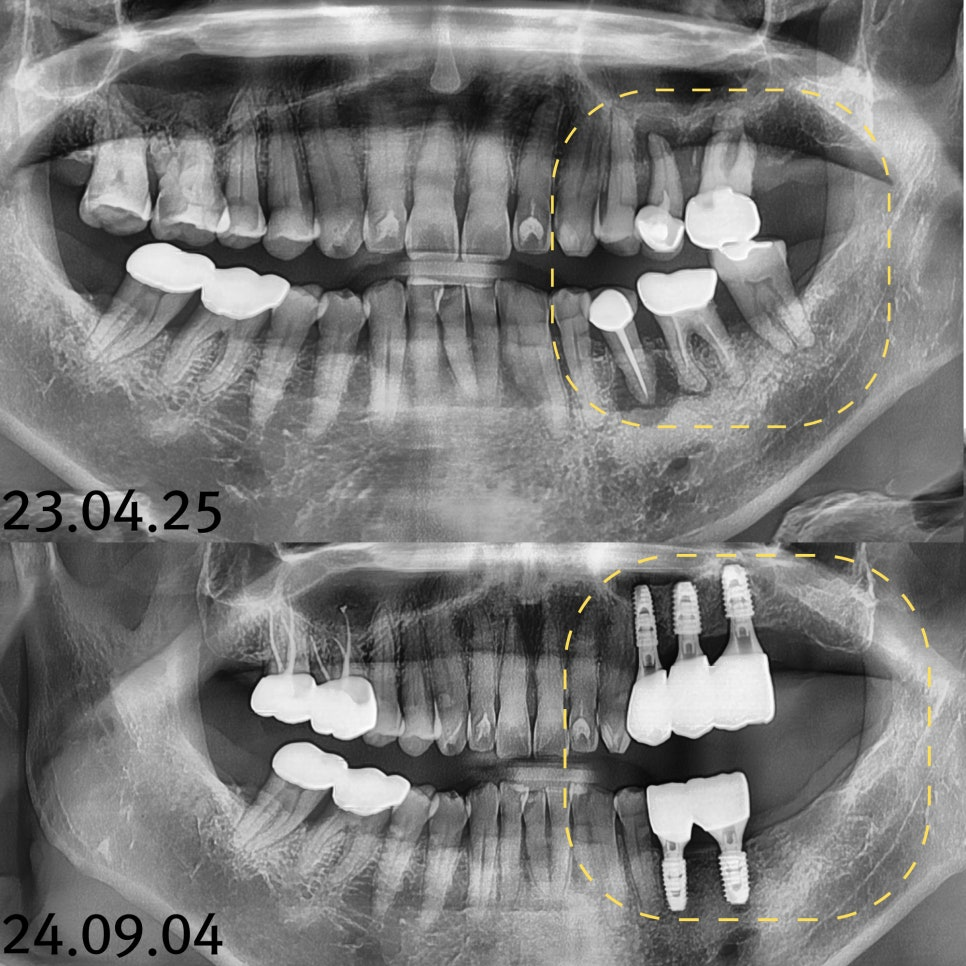

23.04.25 — 치료 전

CT와 파노라마 분석 결과, 치아 뿌리 끝에 염증이 생긴 상태였고 잇몸뼈까지 녹아내리는 만성 복합치주염이 함께 진행되고 있었습니다. 남은 뼈와 잇몸을 지키기 위해 발치를 먼저 진행했습니다.

23.08.25 — 상악동 거상술 전 / 23.11.10 — 시술 후

발치 후 6개월 뒤 내원 시 안쪽 뼈 상태가 좋지 않아 뼈이식과 상악동 거상술이 모두 필요한 상황이었습니다. CT 화면을 직접 보여드리며 근거를 설명드린 뒤, 위쪽을 먼저 진행했습니다.

23.12.15 — 아래 임플란트 식립 / 24.09.04 — 치료 완료

위 회복 확인 후 아래를 순차적으로 진행했습니다. 빠르게 끝내는 것보다 각 단계마다 회복을 확인하며 진행하는 방식을 택했습니다. 총 치료기간은 약 1년 4개월이었습니다.

23.04.25 (치료전)- 24.09.04 (치료후)